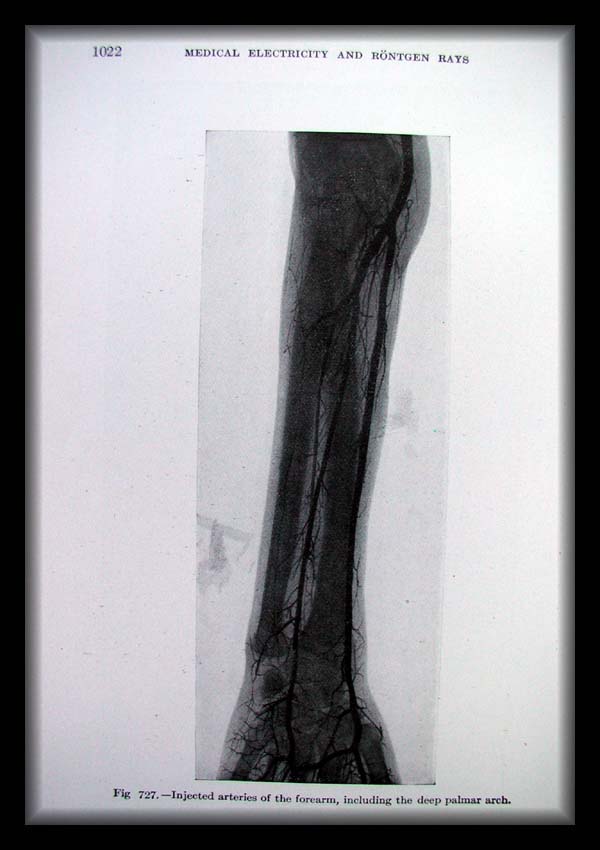

Page1022